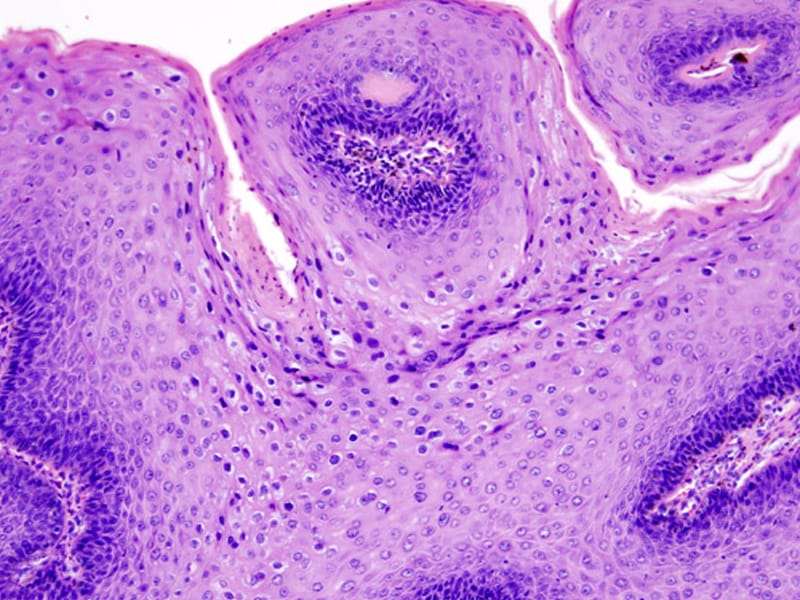

Feigwarzen

Verdampfung

einer Condylomata acuminata

mit den Elektrokauter